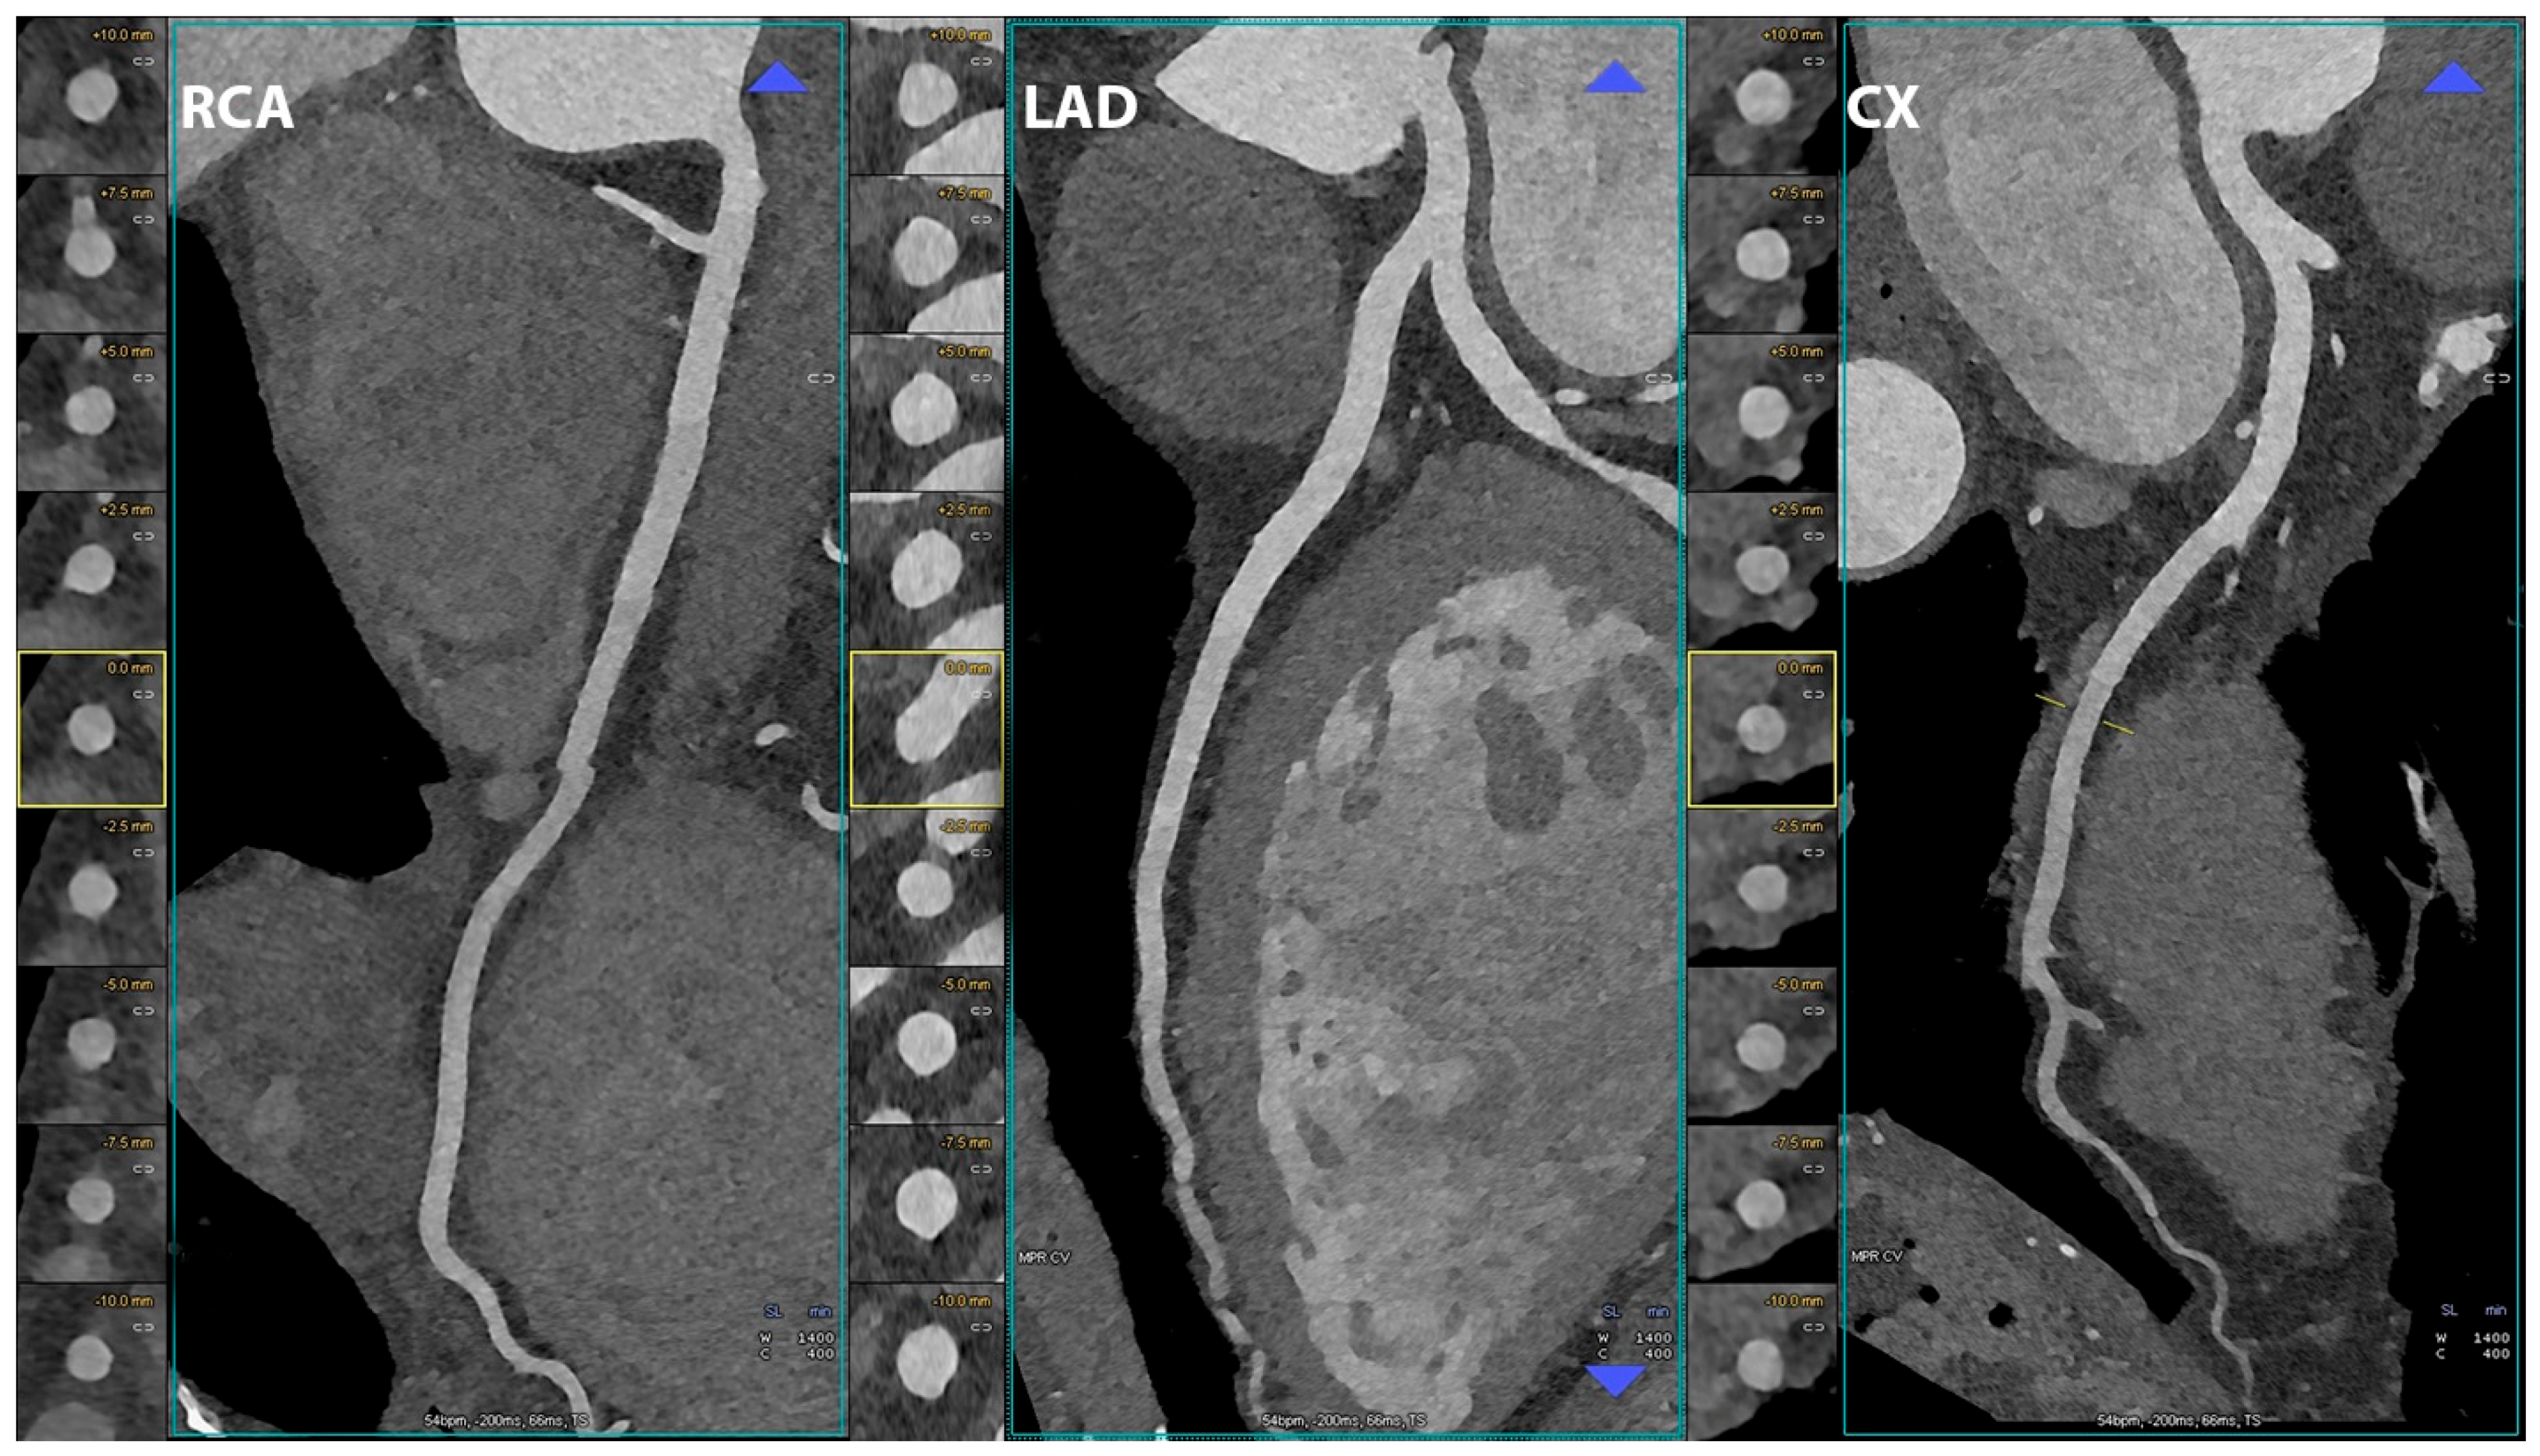

5.1. Coronary Lumen Detection

- Si-Mohamed, S.A.; Boccalini, S.; Lacombe, H.; Diaw, A.; Varasteh, M.; Rodesch, P.-A.; Dessouky, R.; Villien, M.; Tatard-Leitman, V.; Bochaton, T.; et al. Coronary CT Angiography with Photon-counting CT: First-In-Human Results. Radiology 2022, 303, 303–313. [Google Scholar] [CrossRef]